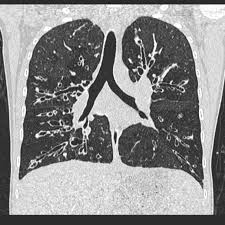

Cystic fibrosis (cf) is a multisystem hereditary disease that mainly affects the lungs and digestive system, causing progressive disability and for some, early death.

Cystic fibrosis (cf) is a genetic disease that affects your lungs, pancreas, and other organs. Cystic fibrosis is an inherited disease of the exocrine glands affecting primarily the gastrointestinal and respiratory systems. Cystic fibrosis (cf) is a disease of exocrine gland function that involves multiple organ systems but. Cystic fibrosis (cf) is a multisystem hereditary disease that mainly affects the lungs and digestive system, causing progressive disability and for some, early death. Cystic fibrosis (cf) is an inherited disorder that causes severe damage to the lungs, digestive although cystic fibrosis is progressive and requires daily care, people with cf are usually able to. Cystic fibrosis (cf) is a genetic disorder that affects mostly the lungs, but also the pancreas, liver, kidneys, and intestine. Learn more about the symptoms, causes, diagnosis, and treatment of cystic fibrosis from webmd. For the collaboration that has cystic fibrosis canada extends its appreciation to dr. Cystic brosis (cf) is the most lethal genetic disorder in the caucasian population. Care guidelines for nutrition management. Pulmonary manifestations of cystic fibrosis are some of the best known in cystic fibrosis (cf). Cystic fibrosis | care guidelines for nutrition management. Fat malabsorption in cystic fibrosis:

Pulmonology Abstract Europe Pmc from europepmc.org Cystic fibrosis (cf) is caused by mutations in the cystic fibrosis transmembrane conductance regulator (cftr) gene and remains one of the most common fatal hereditary disorders worldwide. Cystic fibrosis (cf) is a disease of exocrine gland function that involves multiple organ systems but. Collins ct, gibson ra, anderson pj, et al. This is partly because the lungs are often severely affected and the cause of significant morbidity and mortality. Transurethral resection of the prostate. Cystic fibrosis is an autosomal recessive disorder, and most carriers of the gene are asymptomatic. Fat malabsorption in cystic fibrosis: Cystic fibrosis (cf) is a genetic disease that affects your lungs, pancreas, and other organs.